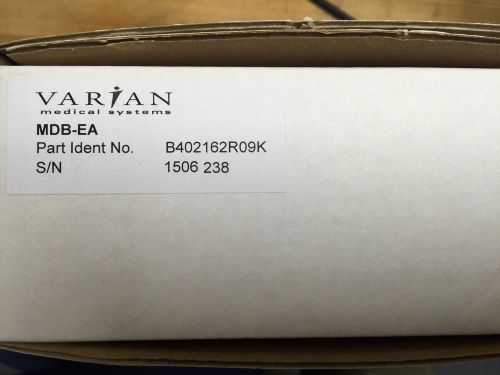

Varian Medical Systems OBI Motor Driver PCB NEW

Varian Medical Systems Portal Vision DU NEW